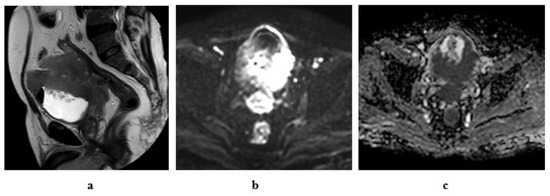

2.6.1. High-Resolution T2-Weighted Imaging (T2WI)

2.6.2. Diffusion-Weighted Imaging (DWI)

2.6.3. Dynamic Contrast-Enhanced (DCE) Imaging

- Stage T1: Intact muscle layer adjacent to the tumor and displays hypointense SI at high resolution T2W sequence without early enhancement on dynamic study.

- Stage T2: Interrupted hypointense line of the muscle layer with early enhancement of the tumor with no extravesical fat invasion.

- Stage T3: irregular outer boundary of the tumor with distortion of the extravesical fat with the same SI of the tumor.

- Stage T4: Tumor infiltrates the surrounding organs or pelvic walls.